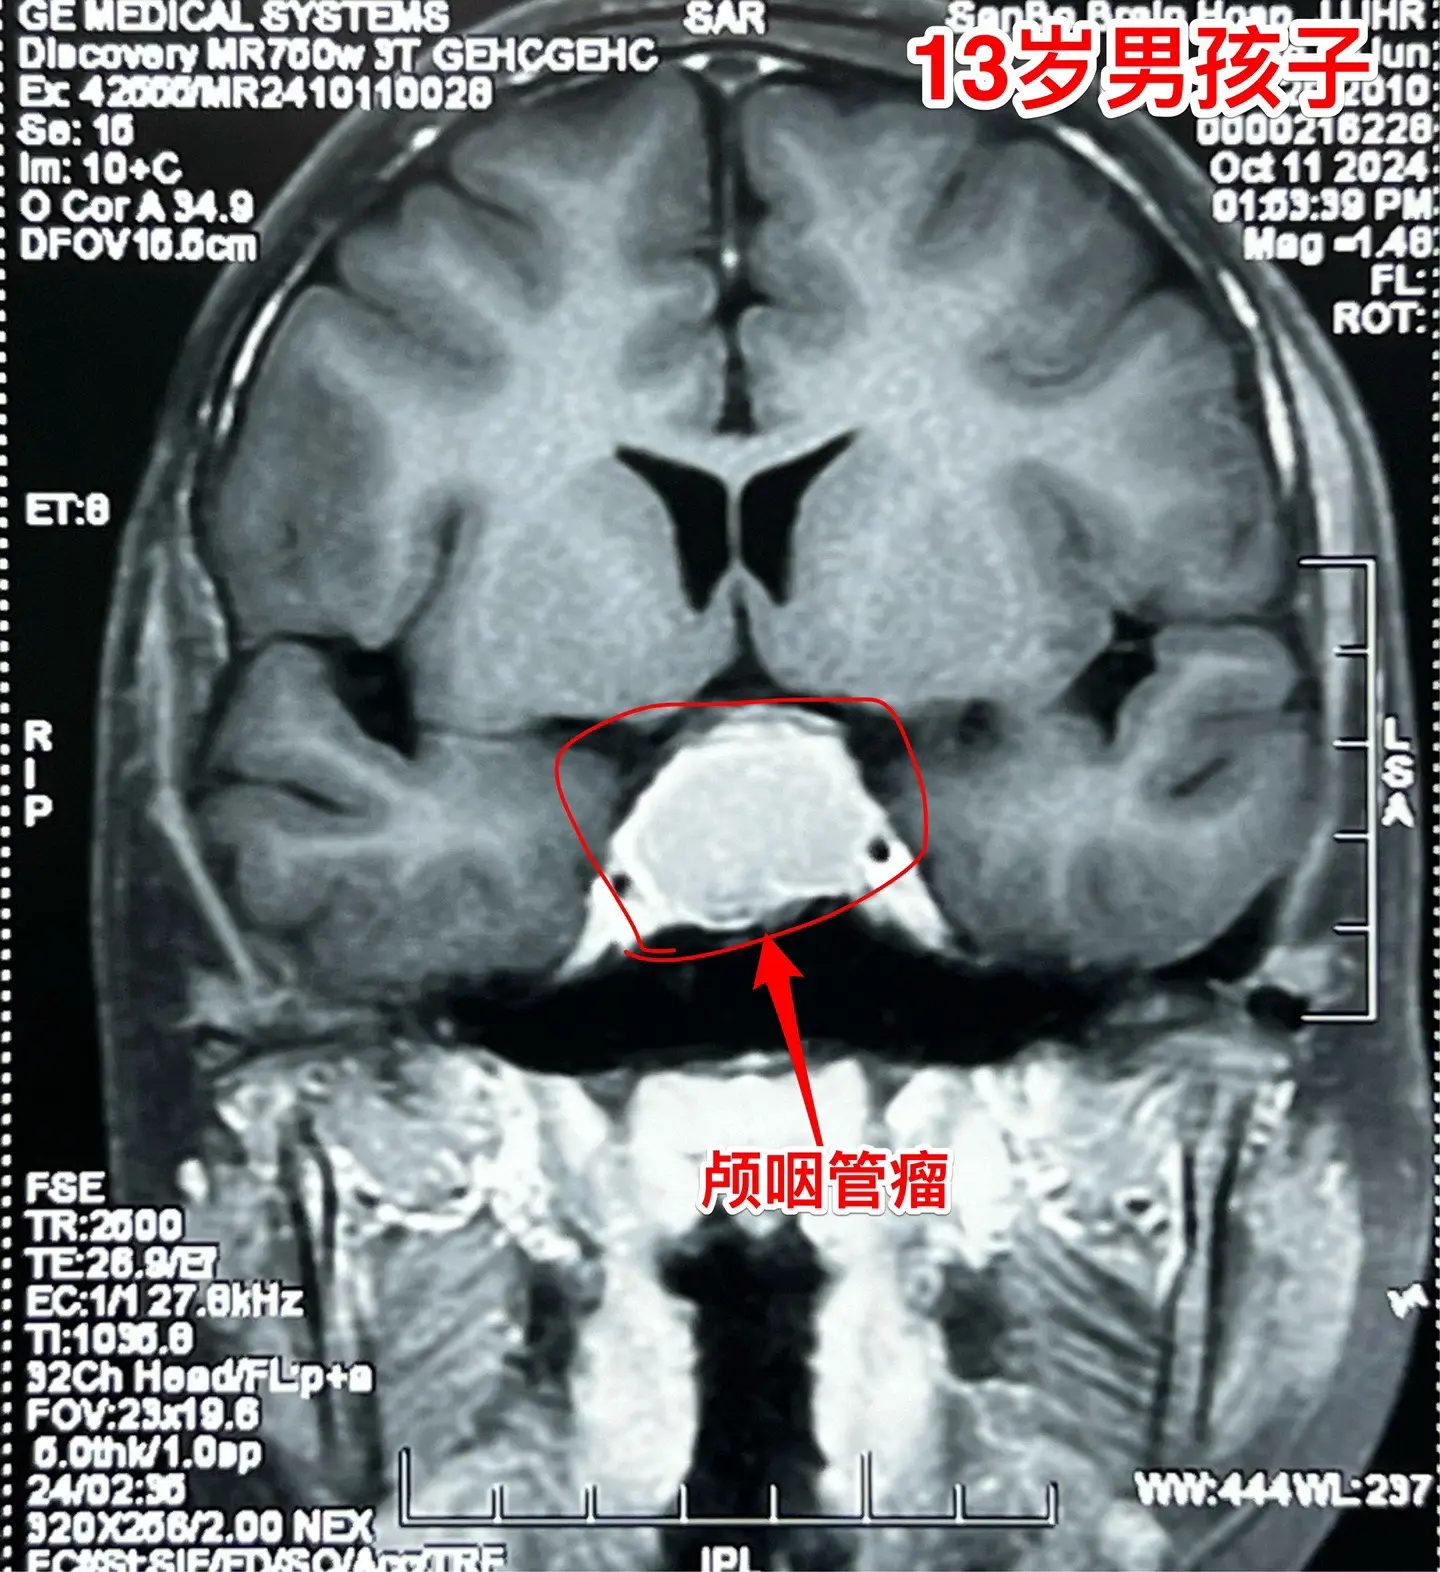

鞍隔下型颅咽管瘤经翼点入路切除合适吗?13岁的山东省菏泽市男孩子,九年前因右眼失明了到医院检查才发现了颅咽管瘤,在外院行手术切除大部分的肿瘤(经翼点入路)。2年前因肿瘤复发在同一个医院再次经原切口切除颅咽管瘤,肿瘤仍未得到完全切除(图3可以看见骨瓣位置)。 肿瘤形态见图,是鞍隔下型的颅咽管瘤。鞍隔下型颅咽管瘤采用翼点入路是很难达到完全切除的,因为垂体窝内的肿瘤处于视觉的死角内,手术医生无法看见。今天(10月20日)我们采用经额底纵裂入路将肿瘤完全切除。手术中意外发现,垂体和垂体柄结构很清晰,得到了保留。 希望肿瘤不再复发。